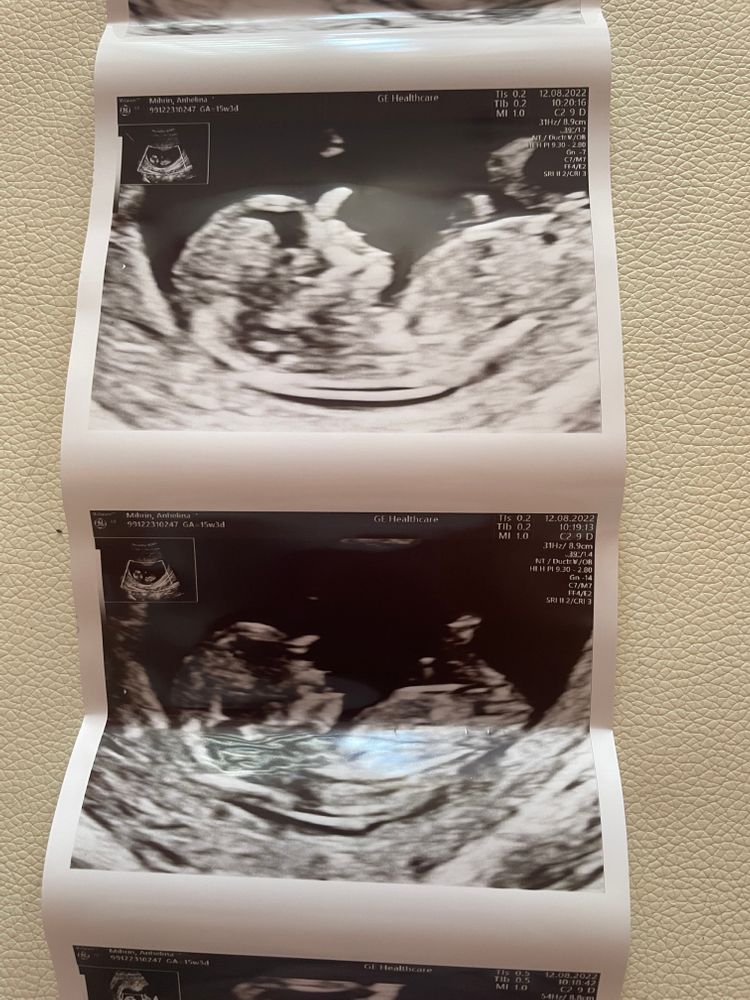

Первый скрининг 🥰

Срок: 11+5

Сегодня увидели нашего малыша. Он казался таким большим🥺 а на самом деле только 5 см🥰❤️

Все замеры в пределах нормы😍 Жалко только, что она даже не предположила пол.🤷🏼♀️ Ждём 21 недели и на 2 скрининг ❤️

Может кто-то сможет увидеть? Мне кажется, что мальчик 🤰🏼

А мне кажется, девочка, если половой бугорок - это то, что я вижу.

Больше похоже на девочку, половой бугорок не вверх, а прямо, прям параллельно.

Девочка скорее всего - половой бугорок горизонтально, у мальчиков он под бОльшим углом торчит.